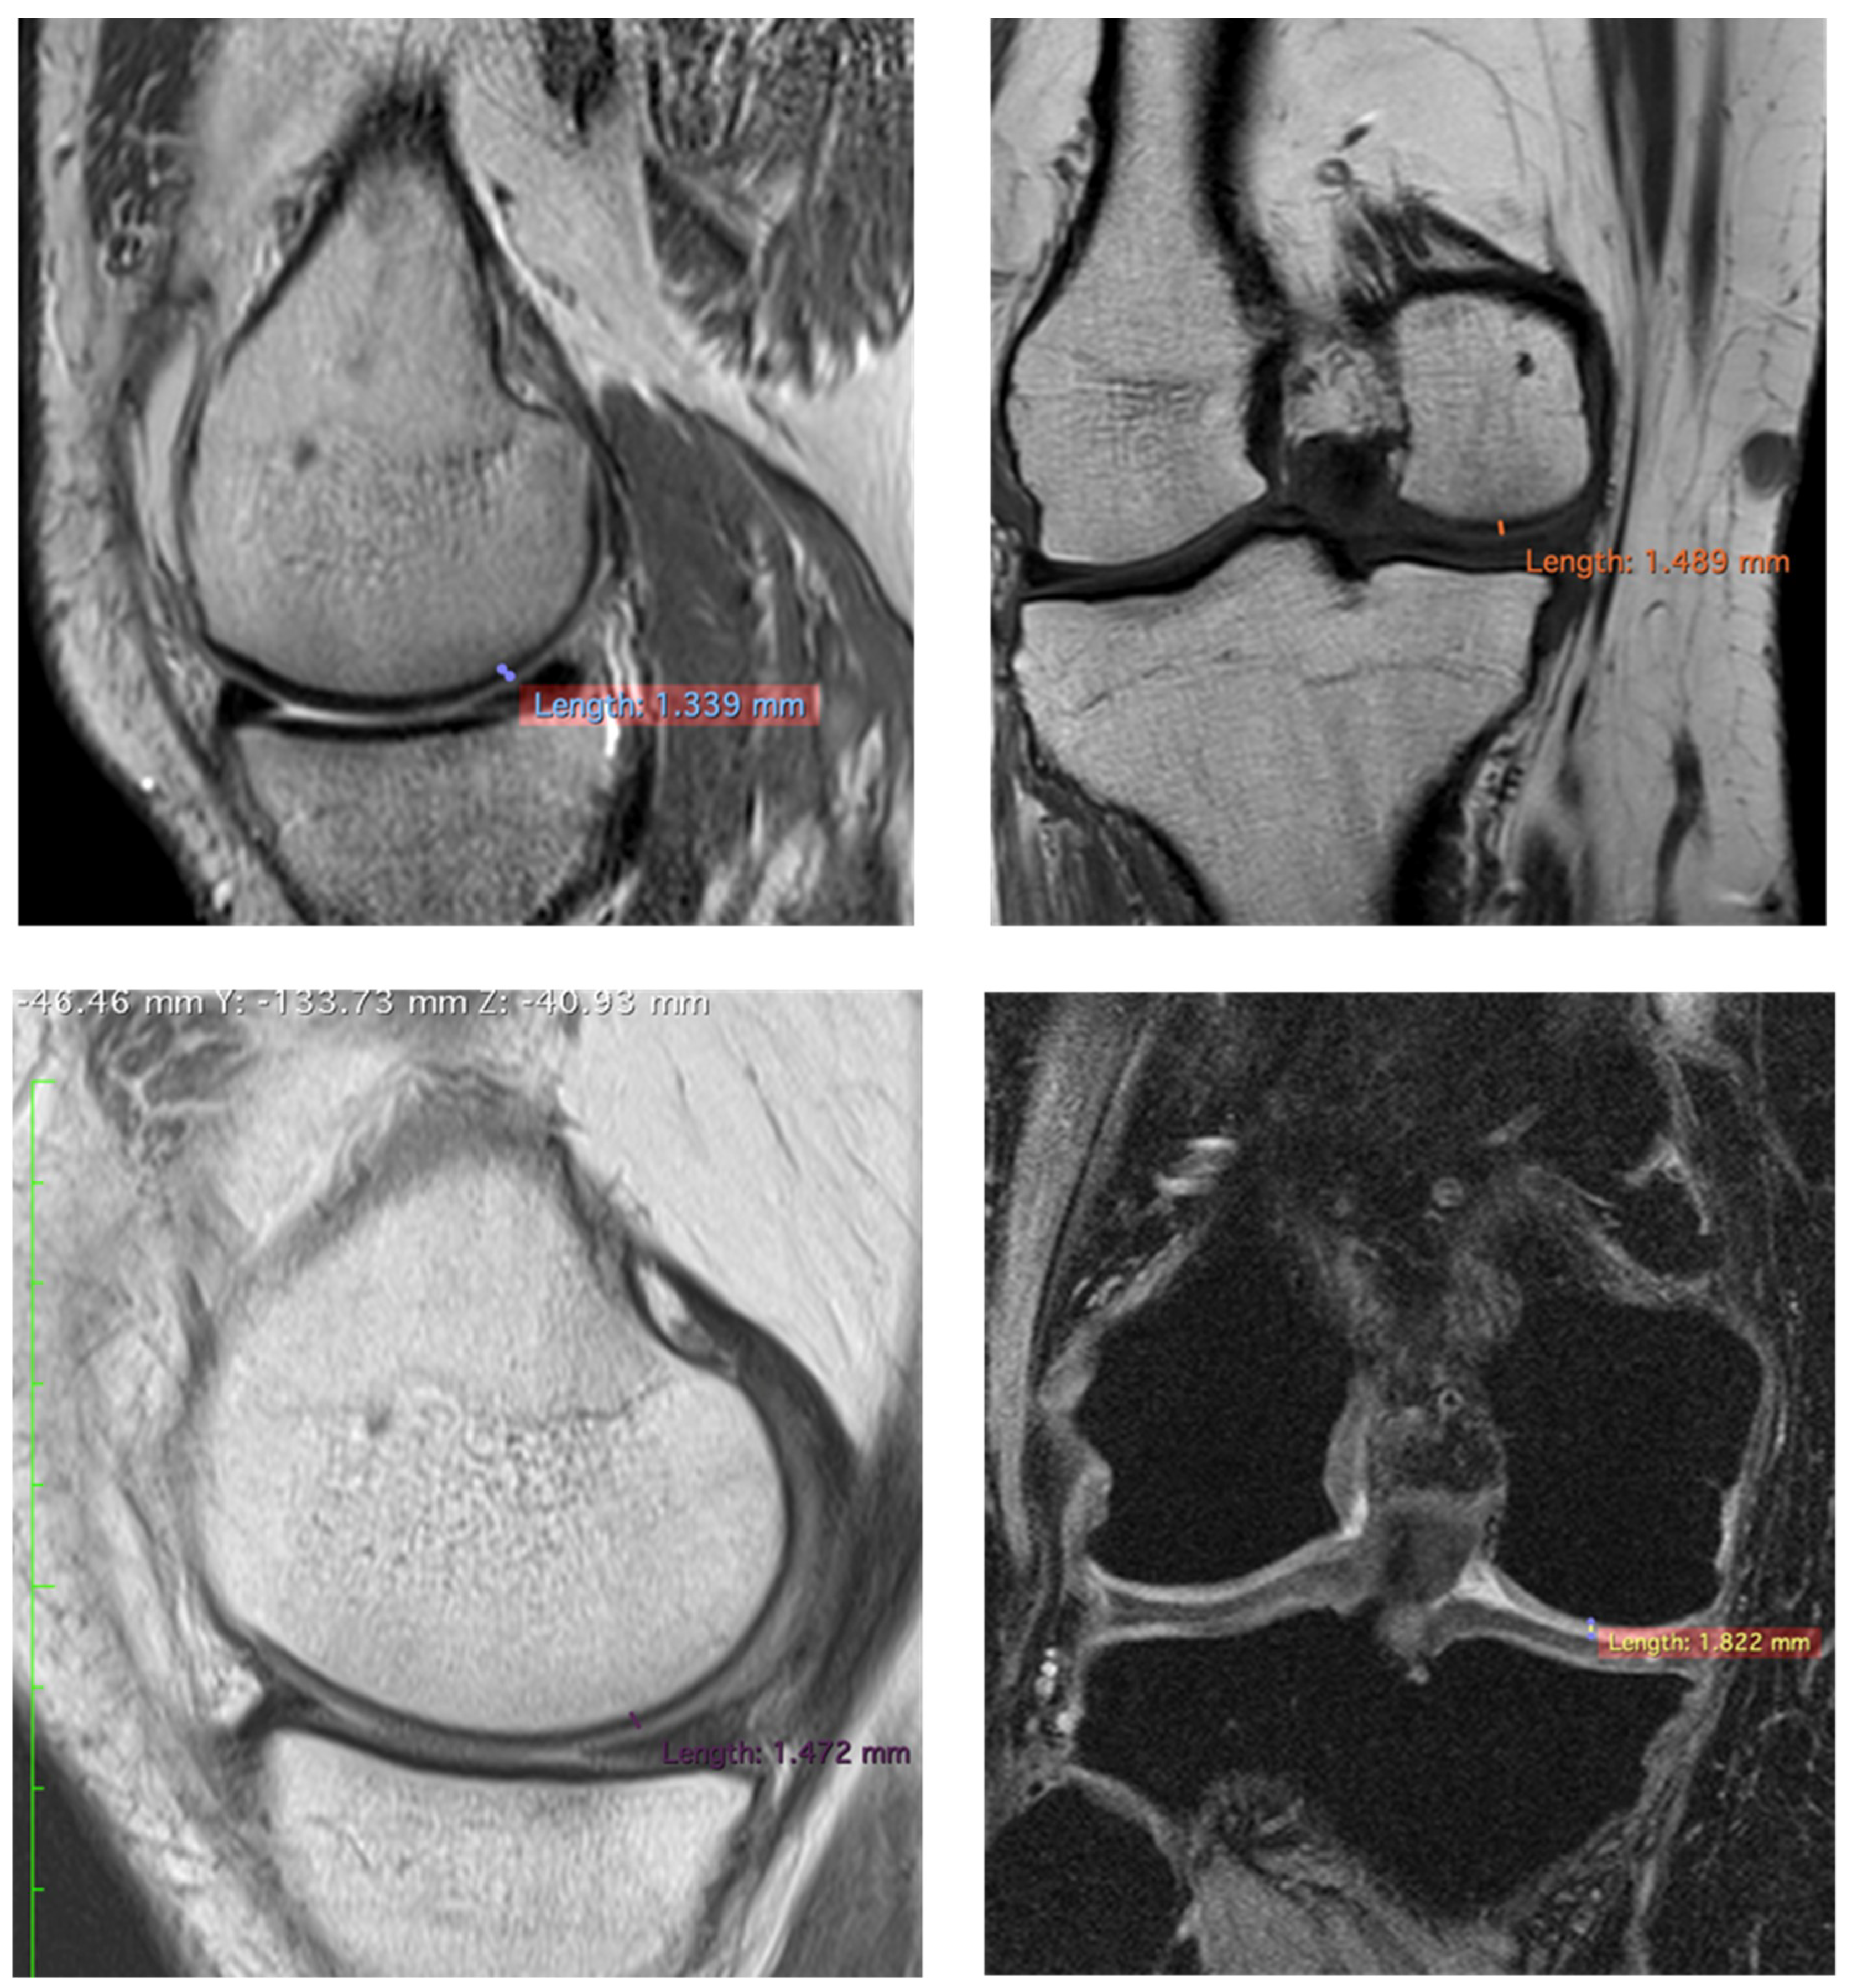

| Patients | Pre/Femoral Lateral Condyles | 3 Years/Femoral Lateral Condyles | Difference |

|---|---|---|---|

| 1 | 1.064 mm | 1.226 mm | +15.22% |

| 2 | 1.339 mm | 1.472 mm | +9.32% |

| 3 | 1.068 mm | 1.263 mm | −14.20% |

| 1 | 1.223 mm | 1.555 mm | +27.14% |

| 2 | 1.489 mm | 1.882 mm | +26.39% |

| 3 | 0.893 mm | 1.914 mm | +114.33% |